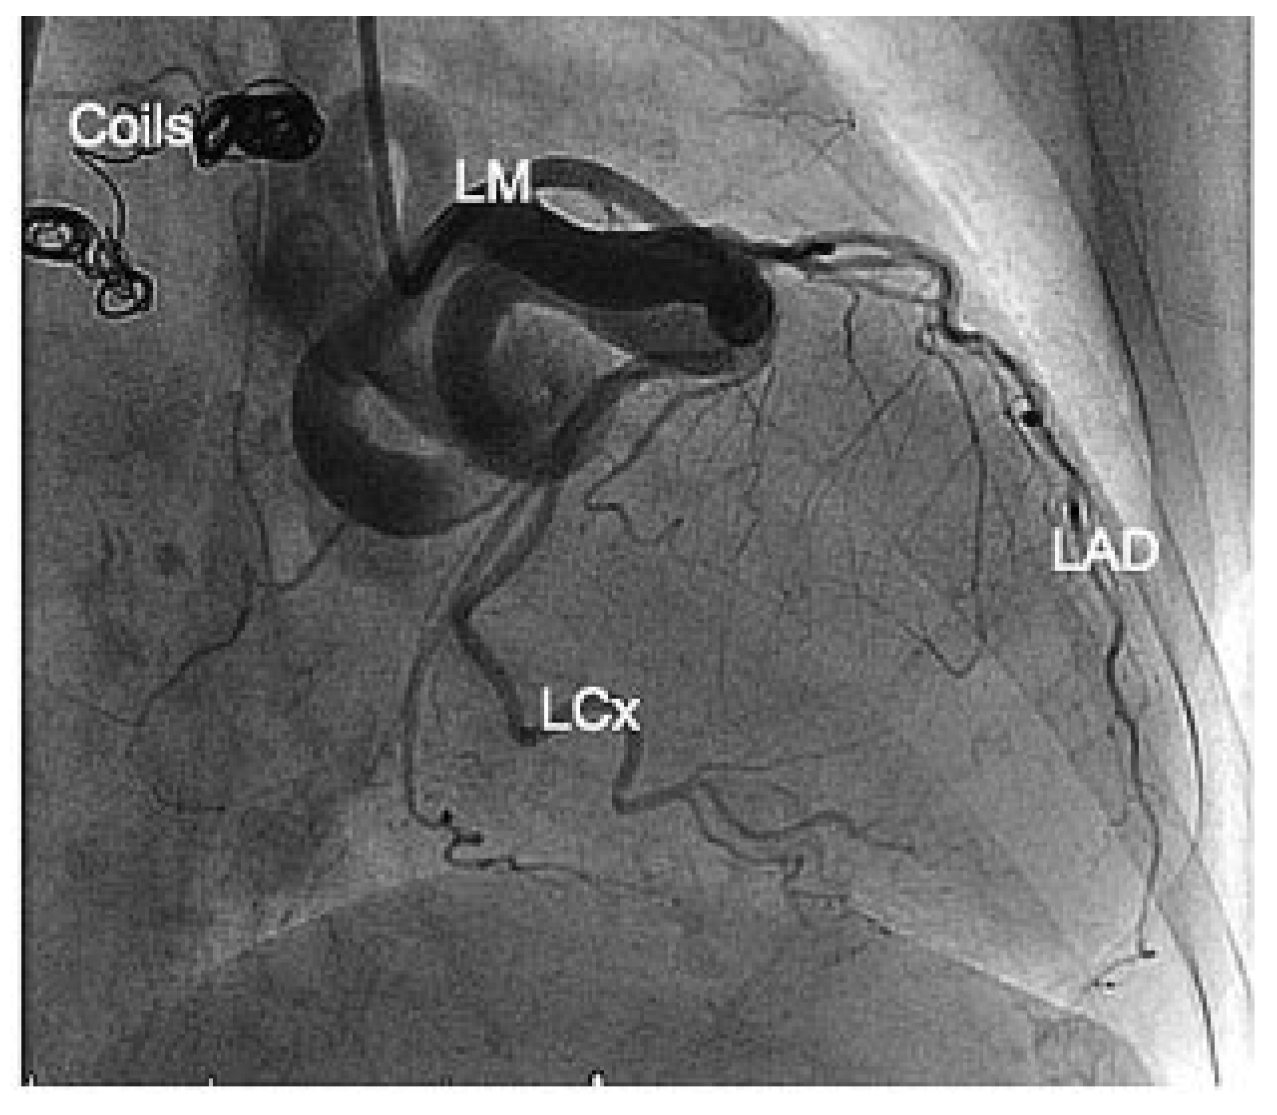

Figure 3.

Anteroposterior view. End result after deployment of 5 coils. LM = left main coronary artery; LAD = left anterior descending artery; LCx = left circumflex artery.

It was considered that the symptoms were at least in part triggered by the coronary fistula. A 6 Fr EBU 4.0 guiding catheter was therefore used to selectively engage the left main stem. The fistula was cannulated with a Fathom (Boston Sci) steerable guidewire (0.016″). Using a Renegade STC 18 microcatheter, and five 2D Interlock coils (Boston Sci; 10 mm × 30 cm, 4 × 8 mm × 20 cm) were deployed within the fistula and successfully clogged the visible blood flow within it (Figure 2B and Figure 3). There were no periprocedural complications and the patient was discharged the following day with a lifelong prescription of aspirin. The risk of atrial fibrillation-related ischaemic stroke was mild (CHADs score of 1 point—2.8%/year) but—mainly due to the patient’s age—the risk of bleeding was high (CRUSADE bleeding risk was 54 points—14%/month). Therefore, and in order to allow complete and definitive closure of the fistula, oral anticoagulation was discontinued for one month. Three months post procedure the patient remained free of symptoms.